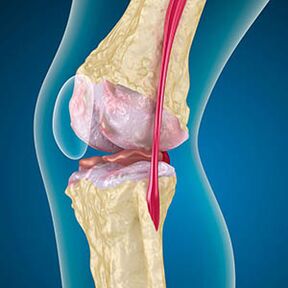

Cu artroza, cartilajul care acoperă marginile oaselor este abraziune sau complet absent. Țesutul deteriorat nu este o sursă de durere, deoarece nu are receptori. Inflamarea în structurile din apropiere provoacă simptome caracteristice.

Corpul continuă regenerarea țesuturilor deteriorate, dar cartilajul crește inegal. Drept urmare, se formează nereguli care rănesc alte elemente ale articulației. Natura osteofitelor este explicată prin compensare pentru cartilajul articular neted. O altă versiune indică faptul că creșterea „Spurs” Este asociată cu o încercare de stabilizare a articulației medial sau laterale din cauza slăbirii mușchilor.